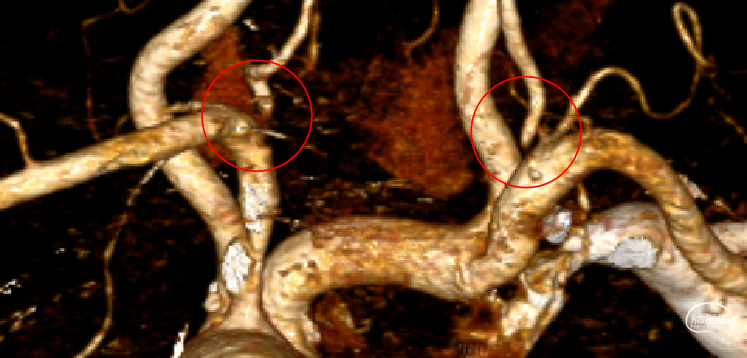

辅助检查(CTA):双侧椎动脉开口重度狭窄,左侧椎动脉为优势动脉,椎动脉颅内段及基底动脉显影良好。

患者左侧椎动脉稍优势,右侧椎动脉开口重度狭窄、次全闭塞,左椎开口重度狭窄。

辅助检查(CTA):双侧椎动脉开口重度狭窄。

患者左侧锁骨下动脉重度狭窄伴斑块形成,左侧椎动脉开口处次全闭塞,右侧椎动脉开口处中重度狭窄,右侧后交通动脉发达。

手术难度与风险评估:患者双侧椎动脉开口重度狭窄,发生缺血性脑卒中风险极高,术前CTA检查提示左侧椎动脉为优势侧,优先行左侧椎动脉开口支架置入预估获益较大,但CTA显示左侧椎动脉开口极重度狭窄近闭塞,术中需仔细寻找血管真腔;

手术难度与风险评估:患者双侧椎动脉开口重度狭窄,且存在卒中风险。后循环梗死可导致瘫痪、昏迷等严重卒中事件。应进一步评估治疗,预防致死致残性卒中事件发生。可在知情同意的前提下行支架成形术,患者及家属已签署知情同意书。